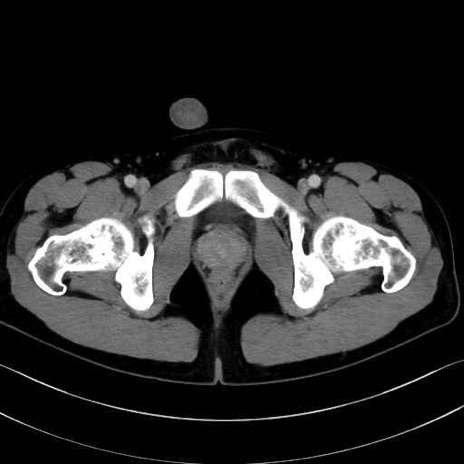

大腿方形筋(Quadratus femoris muscle)のCT画像の解剖

4. 深層外旋六筋(股関節の深部)

大腿方形筋 (Quadratus femoris)